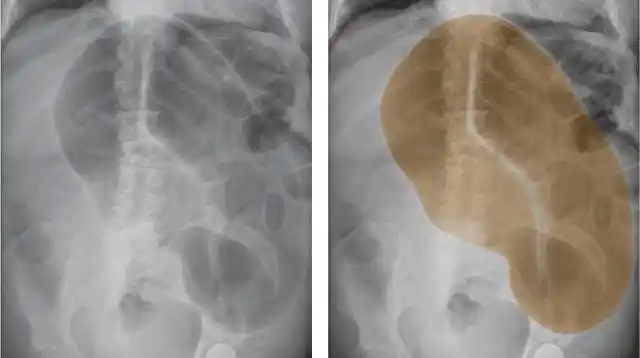

下面我们来看个例子:上为盲肠扭转的图解,盲肠扭转造成盲肠梗阻和肠道

盲肠扭转的影像学表现 | 以影识病